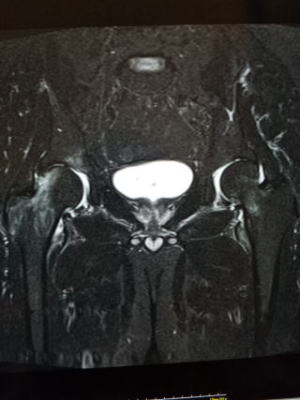

上から6週間目、初診時、初診直後のMRI

症状が出てから日が浅いとレントゲンには何の所見もありません。(写真左)臨床所見として同部に圧痛を認めるのみです。

日にちが2-3週間経過すると仮骨を形成し骨皮質の肥厚を認めます。(写真中央)

MRIは症状出たときから画像に変化があるので、早急に鑑別診断を行う場合にはとても有効です。(写真右)

骨粗しょう症など骨の脆弱性によって荷重部分である骨頭が病的骨折を起こす。高齢者や骨粗しょう症がある場合に、たくさん歩いたり転倒しそうになるなど微少な外傷を起点として大腿骨頭軟骨下の脆弱性骨折が起こるとされる。はっきりとした誘因が無い場合もある。急激な歩行時の股関節部の痛みが生じることが多い。

検査はレントゲンでは初期には変化が無く、精査としてMRIをを行う。鑑別診断としては、特発性大腿骨頭壊死、一過性大腿骨頭萎縮症がある。骨頭が保たれていれば局所の安静、免荷を行う。痛みには消炎鎮痛剤を使用する。骨頭が圧潰するようなら人工骨頭置換術となる。股関節唇損傷を高頻度に合併している。難治性のSIFFHに関節鏡にて関節唇を修復する手術を行い治療する方法が近年、報告されている。